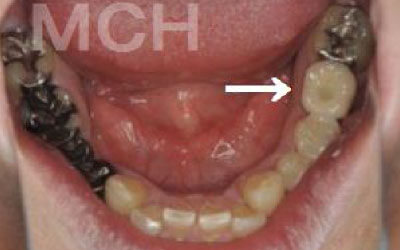

「お口の状態や噛み合わせによって異なるため一概には言えませんが、一般的には奥歯が適しています。

特に、一番奥の歯とその隣の二番目の奥歯が重要です。

噛み合わせの力の60%以上がこの2本の奥歯で支えられているため、ここをしっかりとインプラントで治療するのが理想的です。